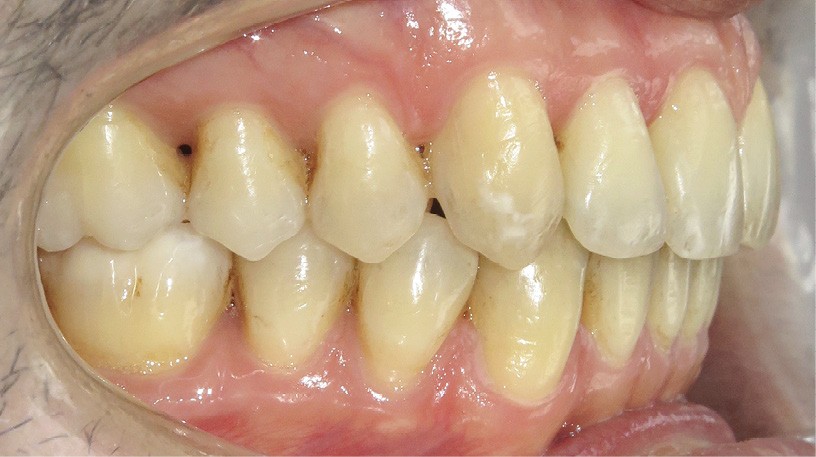

Diagnostic (fig. 1a-i)

Le patient consulte initialement pour des défauts d’alignement. L’examen clinique confirme l’existence d’un encombrement antérieur bimaxillaire, mais révèle aussi la présence d’une Classe II dentaire sévère, d’une exoclusion de la 27 et de troubles parodontaux (peu ou absence de papilles inter-dentaires). Sur le plan squelettique, le patient est relativement équilibré avec un profil harmonieux.